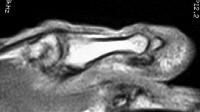

MRI demonstrated ill defined soft tissue replacement of the majority of the distal phalanx:

With contrast enhancement of the transformed area: